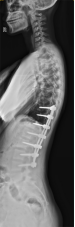

8. 机器人导航辅助下脊柱侧弯矫正技术

脊柱侧弯是一种复杂的脊柱三维畸形,其中以青少年特发性脊柱侧凸最常见。好看视频下载

在浦口地区率先开展机器人导航辅助下脊柱侧弯矫正术,实现了脊柱侧弯手术准确、微创、智能化的突破,获得了良好的效果。还有老年人退变性侧弯,机器人亦可精准置入困难椎弓根螺钉,误差只有0.3mm。